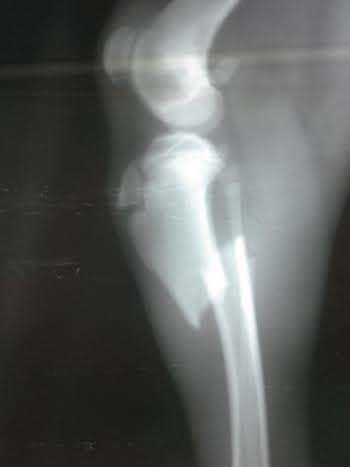

In the times of the dictatorship, you could see large signs saying: “Not a day without fish!” (later, of course, there wasn’t any fish to be found either). This is the way with us too: “No day without suffering and pain. ” Another little soul was lying by the road, after a driver from hell ran him over… Desperate calls began to come our way, asking us to help this poor dog who couldn’t walk and was full of wounds, on top of being emaciated. Now he is at the clinic, with lots of investigations going on, as well as support treatments, X-rays, and he will be going for surgery. For that reason, we are asking you again to support us, so that, in our turn we could save him. We always say that not all people can donate money, but they can spread the news on Facebook, or messengers, or emails. Alone we can’t cope with so many needs, and we need all the help, however small. IT MATTERS SO MUCH to this innocent souls! THANK YOU for caring!